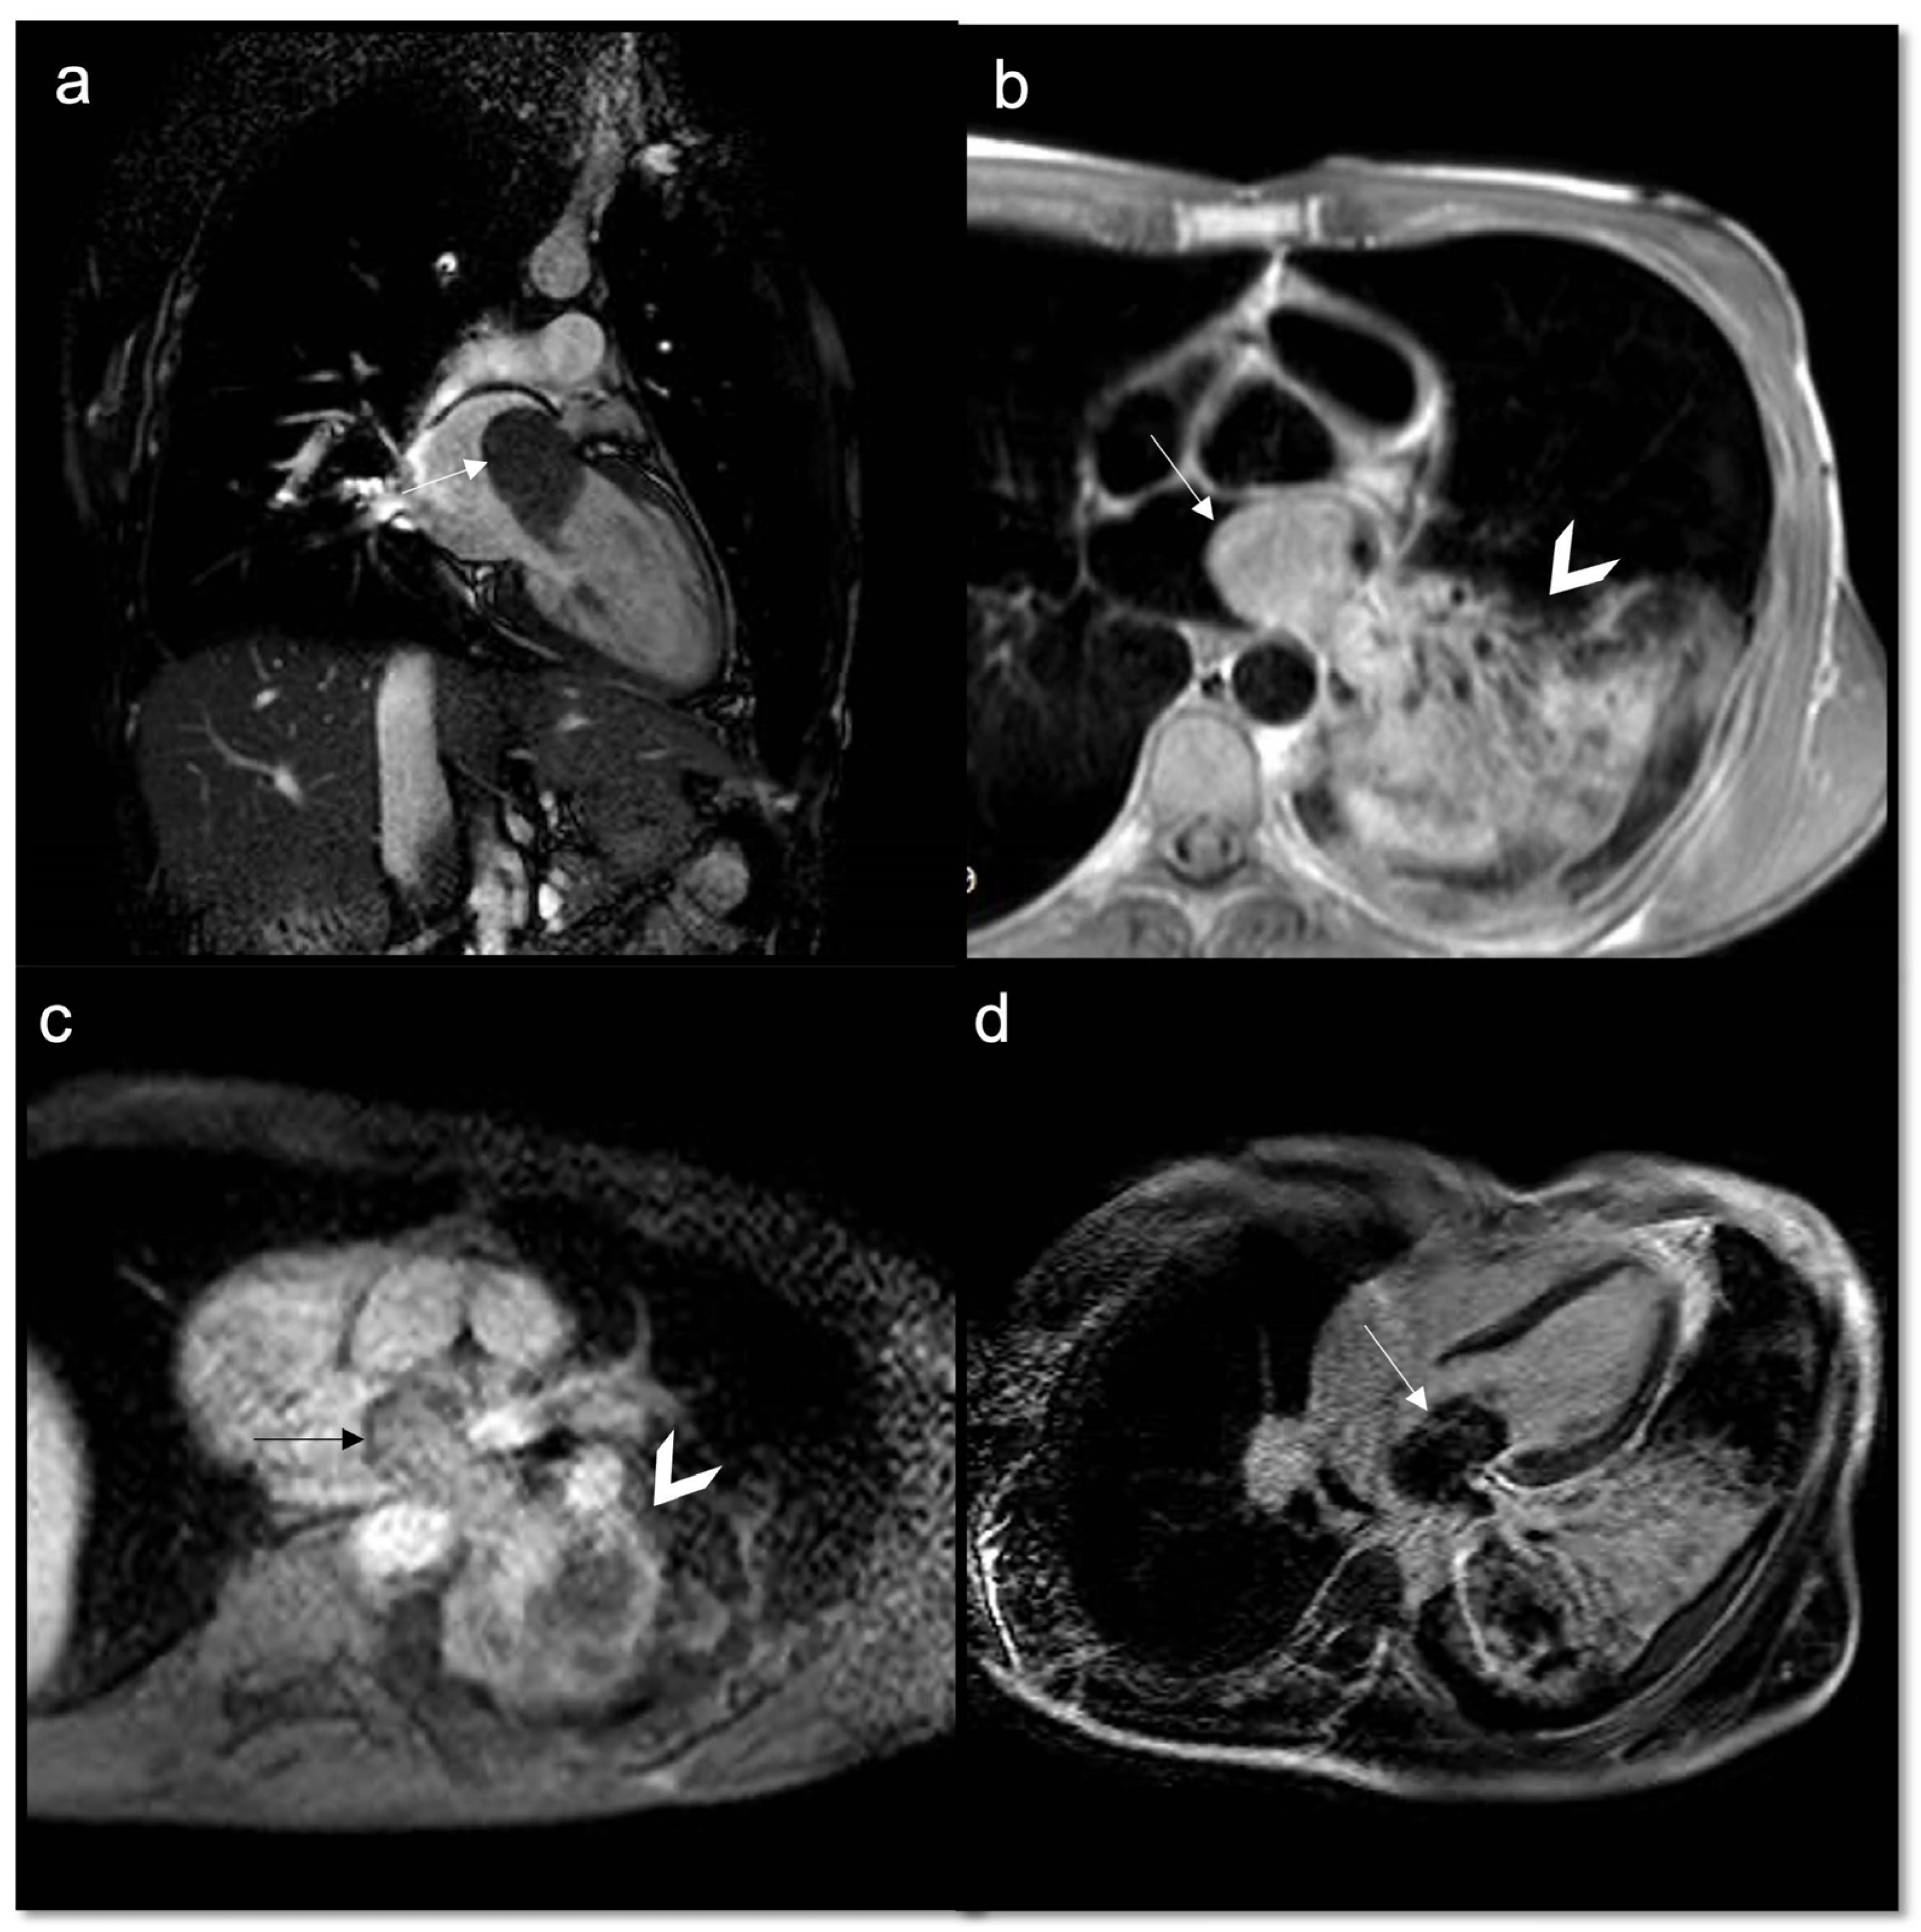

7.2.5. Late Gadolinium Enhancement (LGE)

- Malignant masses often show heterogeneous enhancement; typically, angiosarcoma shows early avid enhancement as it is richly vascularized.

- Trombi due to their avascular nature appear non-enhanced.

- Organized thrombi may show peripheral enhancement on LGE images, owing to their fibrous content.